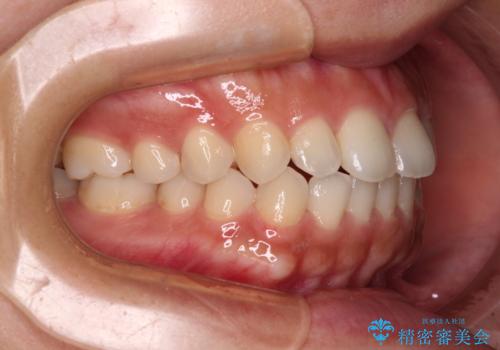

インビザラインを用いた上顎の部分矯正

- 上顎前歯の叢生を気にして来院された患者様です。

下顎前歯や上下奥歯の咬み合わせには殆ど問題がないため、上顎前歯のみを矯正する治療を提案しました。

ワイヤー装置でもインビザラインでも可能でしたが、前歯のみをきれいに排列するのであればインビザラインの方が仕上がりが良いので、インビザライン・ライトにて治療を行うこととしました。